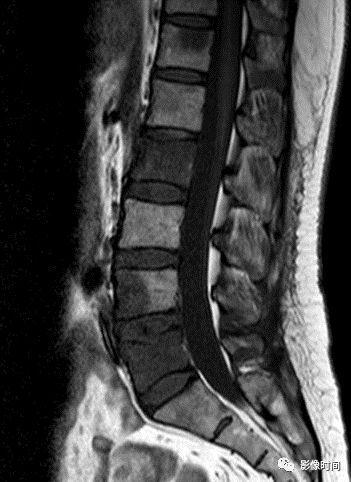

8牙膏征

牙膏征(Toothpaste sign)

牙膏征是指在矢状位脊柱影像中,脱出的椎间盘突入椎管内并向下游走,形似被挤出的牙膏而得名。

典型病例

矢状位 T2WI 像示脱出的椎间盘突入椎管,形似被挤出的牙膏,呈牙膏征(箭示)。